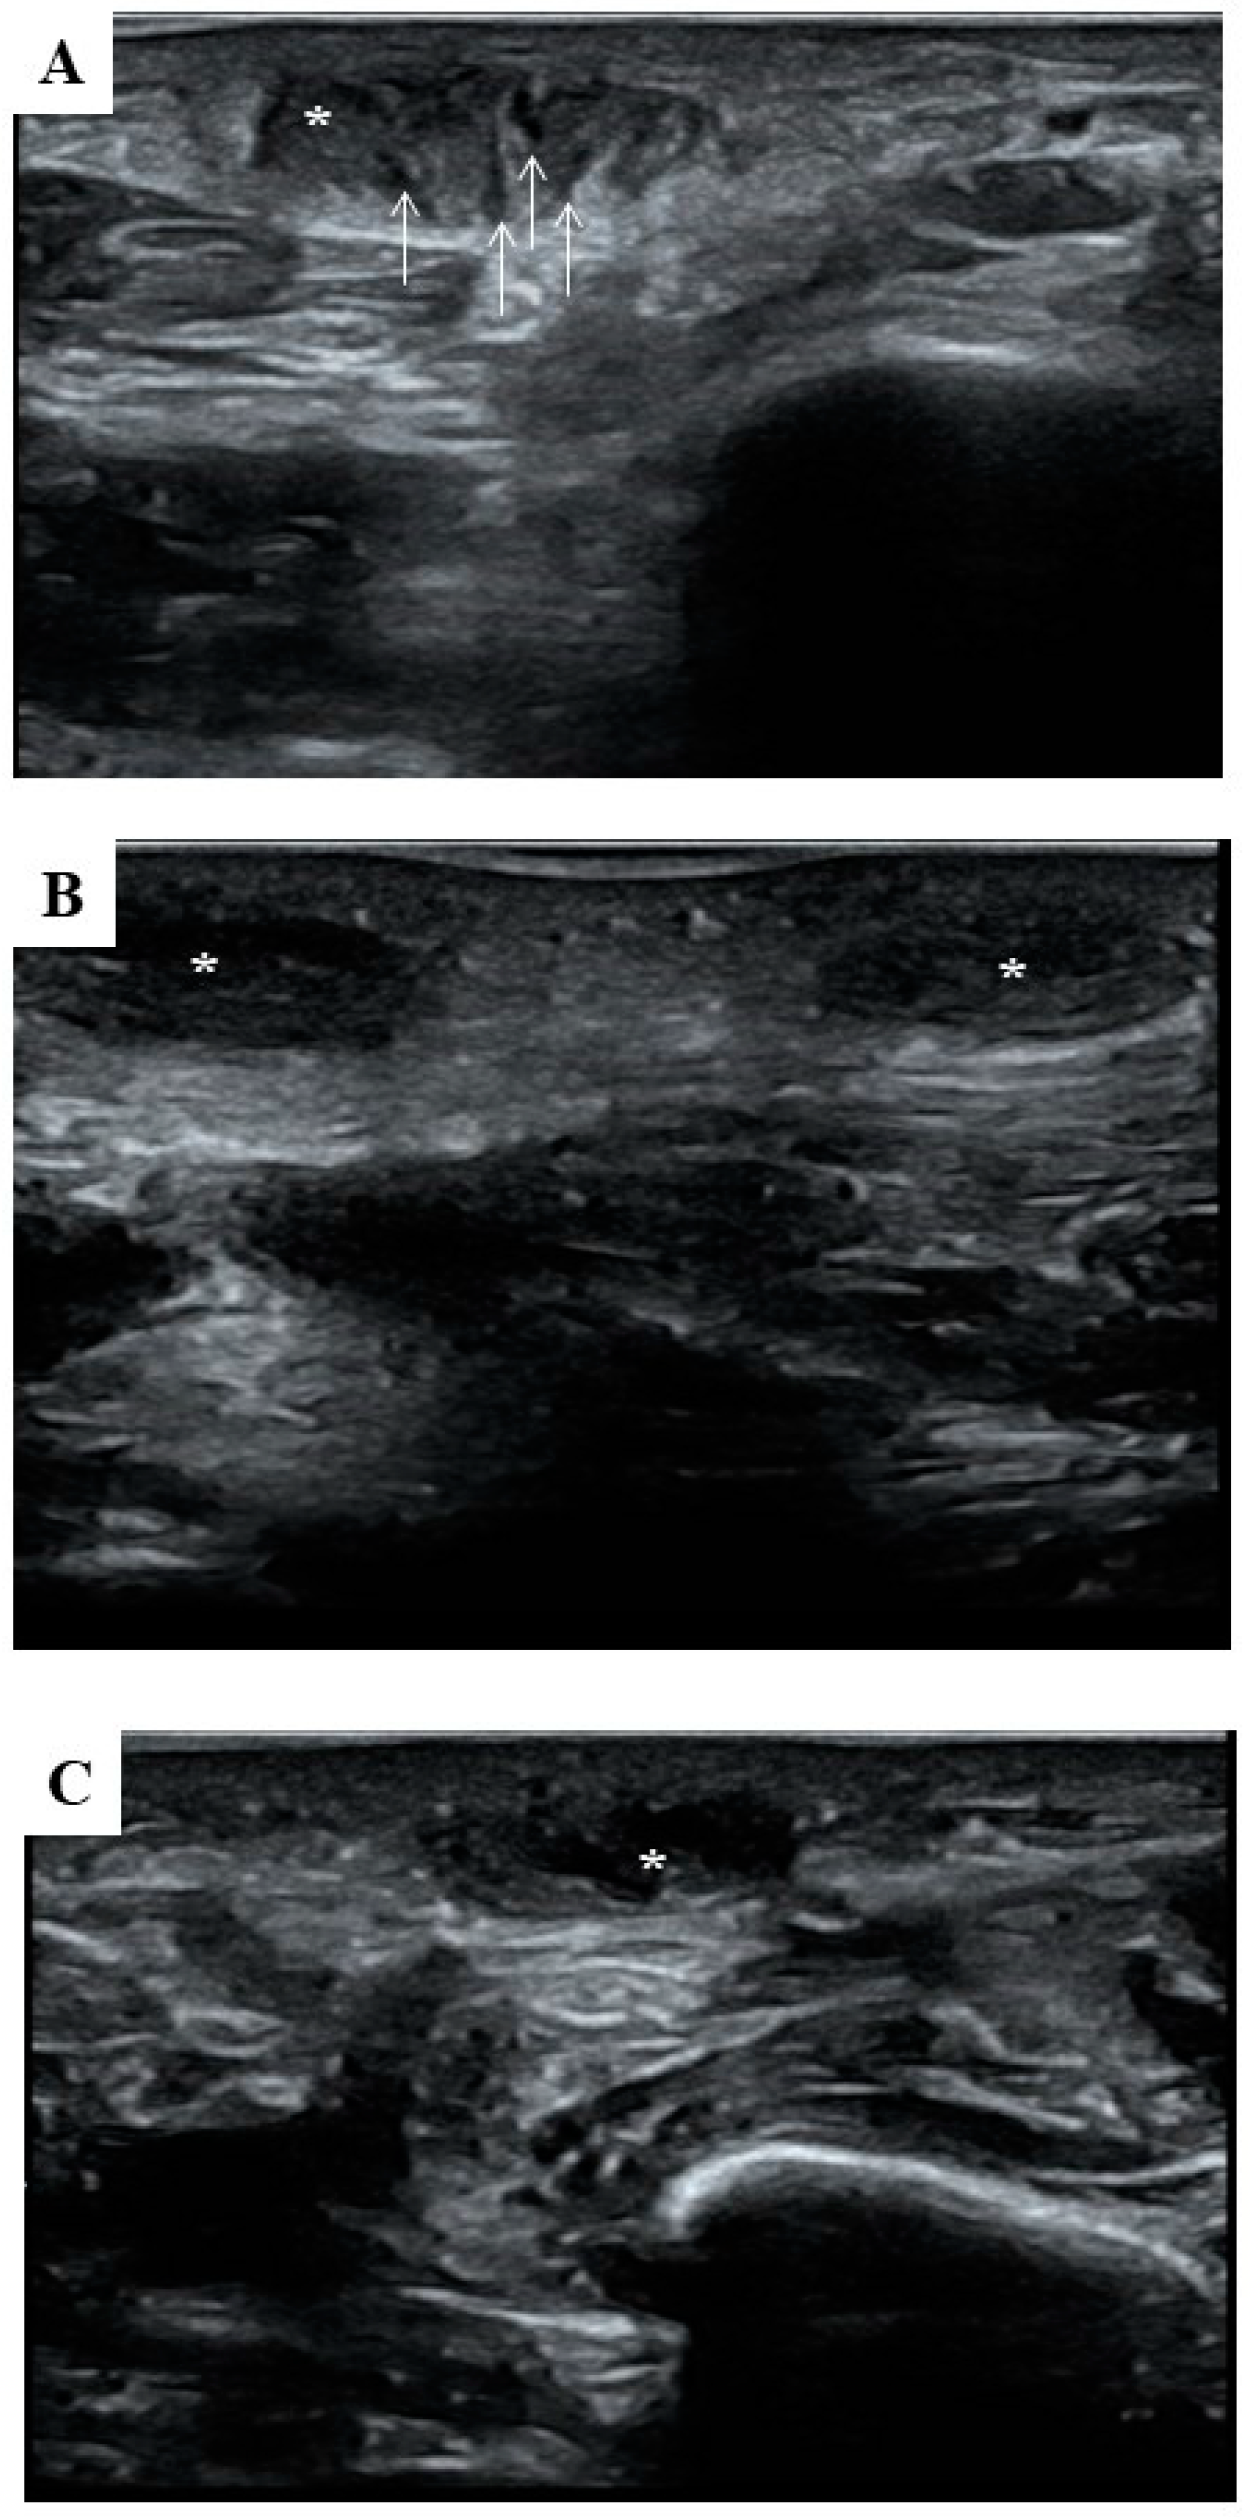

| Timing | Diameter (cm) | Echogenicity | |

|---|---|---|---|

| Maximum | Minimum | Mean Grey Value | |

| T0 | 1.46 ± 0.01 | 0.54 ± 0.01 | 0.87 ± 0.05 |

| T1 | 1.48 ± 0.02 | 0.54 ± 0.01 | 0.84 ± 0.04 |

| T2 | 1.46 ± 0.01 | 0.52 ± 0.01 | 0.50 ± 0.04 * |